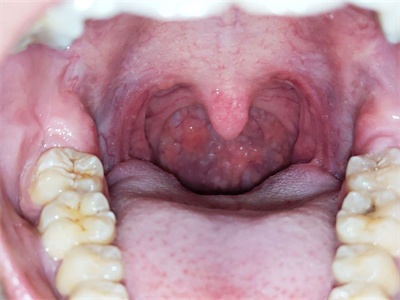

慢性肥厚性咽炎检查可见黏膜充血、增厚,咽后壁淋巴滤泡显著增生,多个散在突起或融合成块,咽侧索亦充血肥厚。